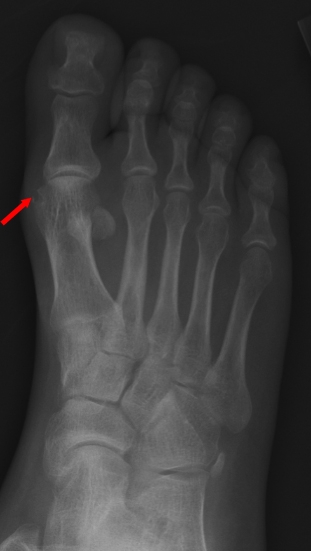

Gout Xray

Gout causes an inflammatory effusion and needle-shaped, negatively birefringent crystals; x-rays characteristically show punched-out erosions with a rim of cortical bone.